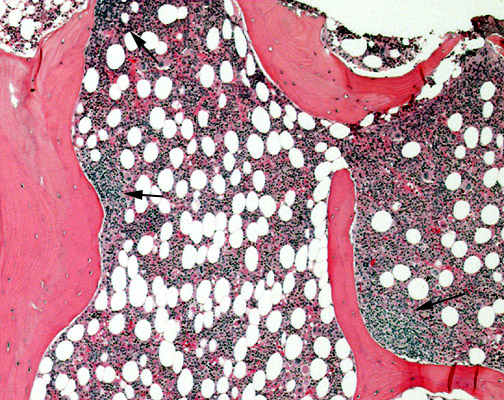

This is a low-power view of low-grade follicular lymphoma metastatic to the marrow. Note that the deposits, indicated by black arrows, tightly adhere to the trabeculae.